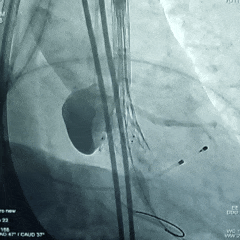

瓣膜初始定位

瓣膜展开至工作位

瓣膜工作位评估